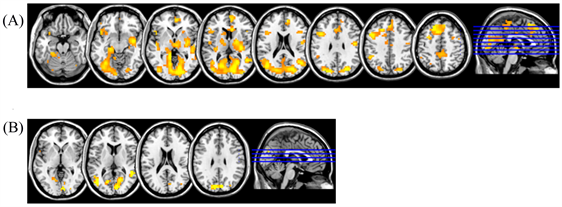

Group analysis of fMRI data in healthy persons is presented in Figure 1(A) and Figure 1(B). FMRI response changes during right-hand movement (Figure 1(A)) demonstrated the activation of the contralateral, left sensorimotor cortex in the precentral and postcentral gyri, a supplementary motor area in the medial parts of the superior frontal gyrus, and ipsilateral hemisphere of cerebellum.

An analysis of group mean fMRI responses to left-hand movement (Figure 1(B)) revealed only one main activation area in the sensorimotor area of the contralateral right hemisphere. This phenomenon can be explained by the fact, that individual fMRI responses while moving non-dominant left hand are more variable than those with right-hand movement. Some subjects have no activation area in the cerebellum ipsilateral hemisphere, while the sensorimotor cortex of the ipsilateral hemisphere and supplementary motor area are activated in others.

Figure 1. Group-average fMRI responses for healthy subjects during (A) right-hand movement and (B) left-hand movement (n = 20, t = 3.53, p(unc) < 0.001, with cluster correction for multiple comparison р(FWE-corr) < 0.05).

Figure 2. Examples of individual fMRI responses during right-hand (A) and left-hand movement (B) in healthy subjects Sch. and G.